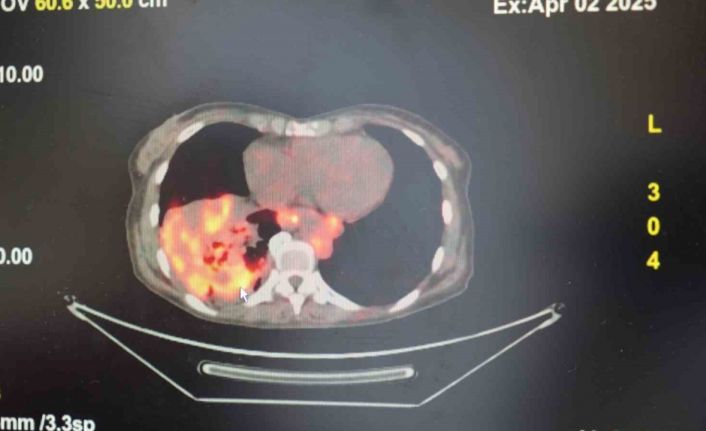

’Sigarasız akciğer kanseri’ vakalarında dikkat çeken artış

Göğüs Hastalıkları Uzmanı Prof. Dr. Şevket Özkaya, son yıllarda sigara kullanmayan bireylerde de akciğer kanseri vakalarının dikkat çeken bir oranda arttığını belirterek, özellikle kadınlarda görülen adenokarsinom tipi akciğer kanserinin artış gösterdiğine dikkat çekti. Bu konuda yapılan son araştırmalara değinen Özkaya, akciğer kanseri teşhislerinin yaklaşık yüzde 20’sinin hiç sigara içmemiş bireylerde konduğunu söyledi.